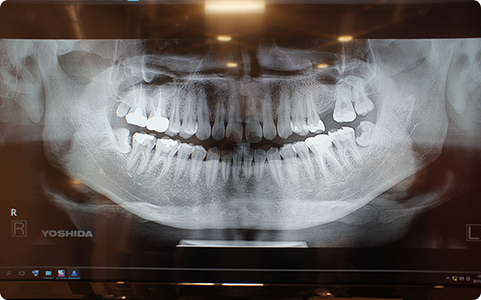

デジタルレントゲン

従来のレントゲンに比べて少ない放射線被ばく量で、鮮明なレントゲン画像を撮影することができます。撮影直後に画像は確認でき、より正確な診査・診断に役立てることができます。